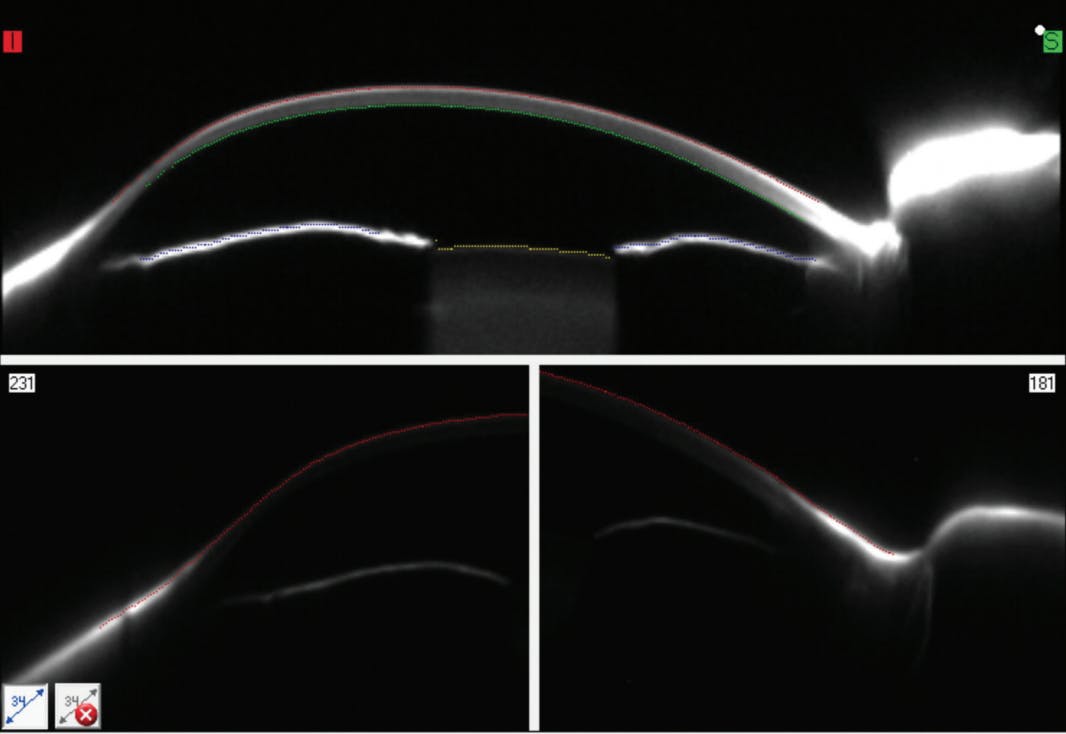

The Oculus Pentacam CSP software captures the corneal and scleral sagittal values by taking cross-sectional meridional scans while rotating. This creates a matrix of sagittal data (100K+ data points) from the center of the cornea to a diameter of approximately 16.5 mm. It is important to have the patient eyelids out of the way so the camera can capture the superior and inferior sclera and the ability to get the lids out of the way will determine how large an area can be scanned. It can be seen how holding the inferior lid out of the way while the Oculus Pentacam CSP software is capturing the inferior sclera in Figure 5 aids in obtaining this sagittal data (lower left image).

Wave imports all of the scanned sagittal data to create a virtual model of the cornea and sclera to be used as a reference surface to design a unique lens. Utilizing the Wave design software, the first pair of scleral gas permeable lenses was designed for the patient and can be seen in Figure 6.